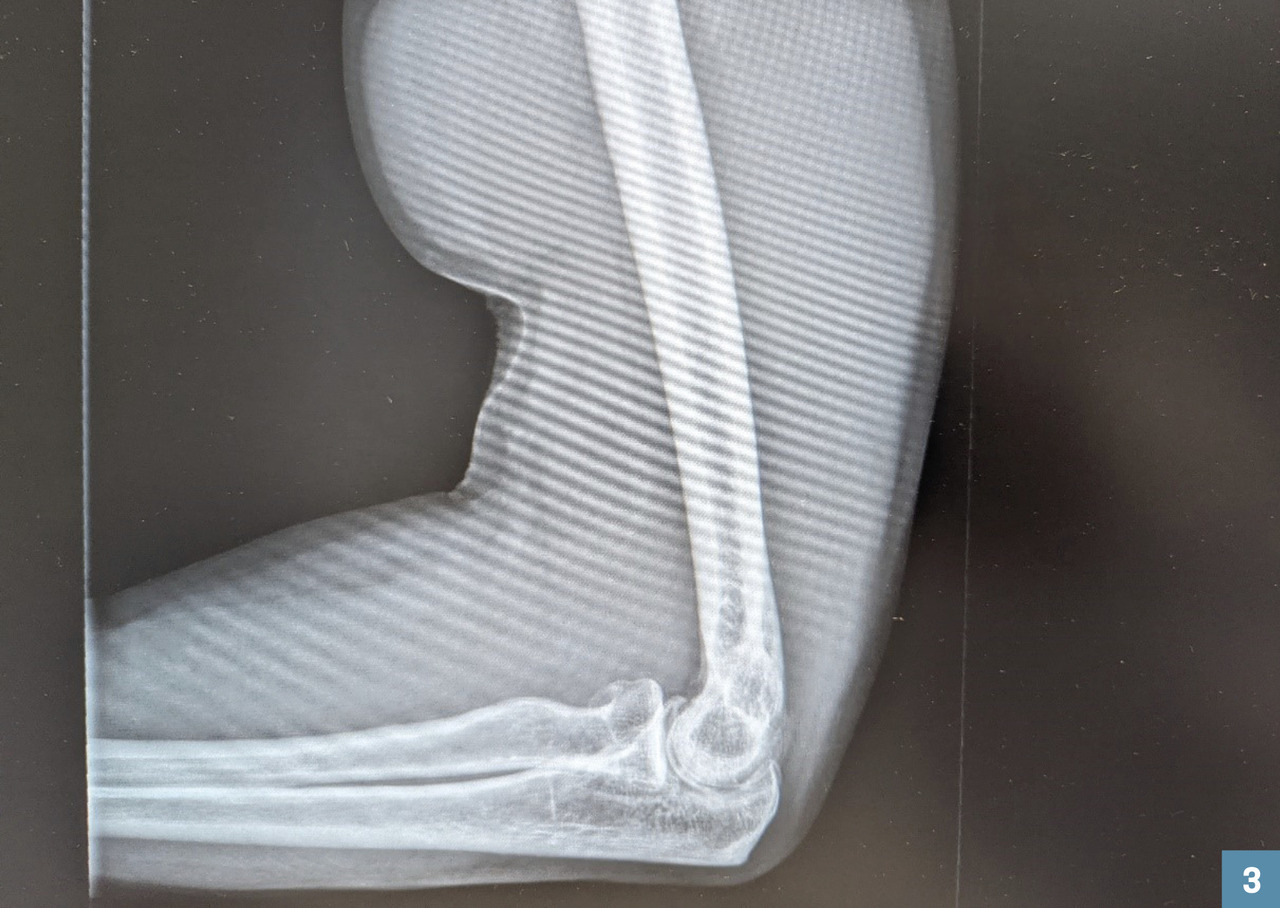

La radiographie – à réaliser systématiquement pour rechercher un éventuel arrachement de la tubérosité radiale –, bien que normale sur le plan osseux, montre de façon encore plus évidente la rétraction du biceps (fig. 3).